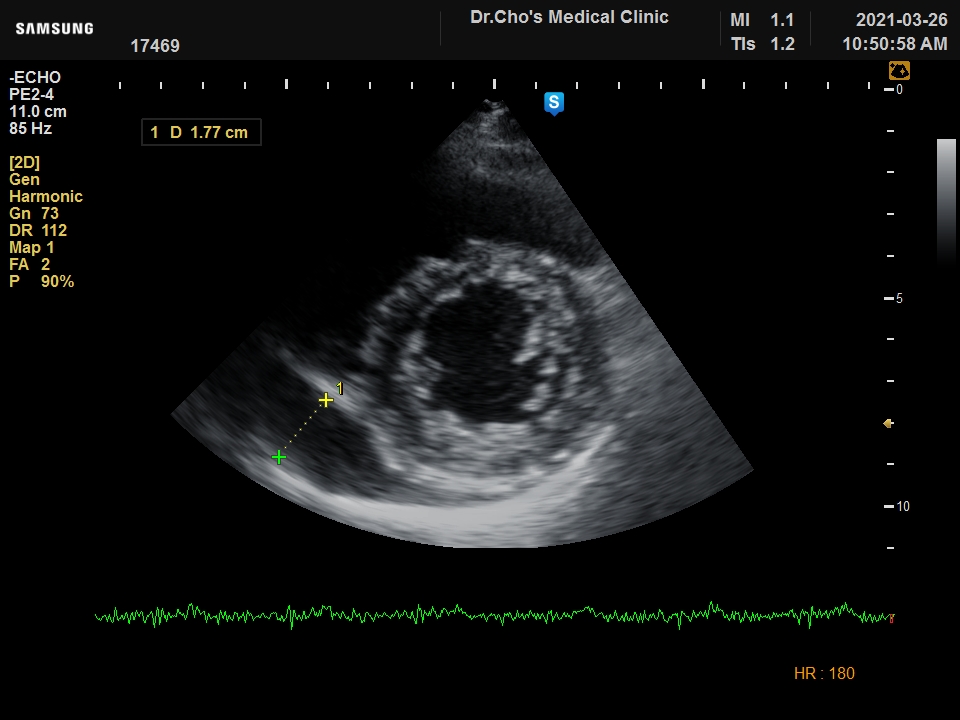

ÃÊÀ½ÆÄ°¶·¯¸®

¿ì½É½Ç °æ...

ºñÈļº ½É...

È®À强 ½É...